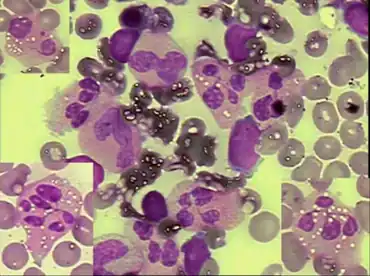

- Bone marrow hypercellularity

Patients exhibit increased susceptibility to bacterial and viral infections, especially from common serotype human papilloma virus, resulting in warts on the hands and feet starting in childhood. Myelokathexis refers to retention (kathexis) of neutrophils in the bone marrow (myelo). In addition, lymphocytes and IgG antibody levels (gammaglobulins) are often deficient.